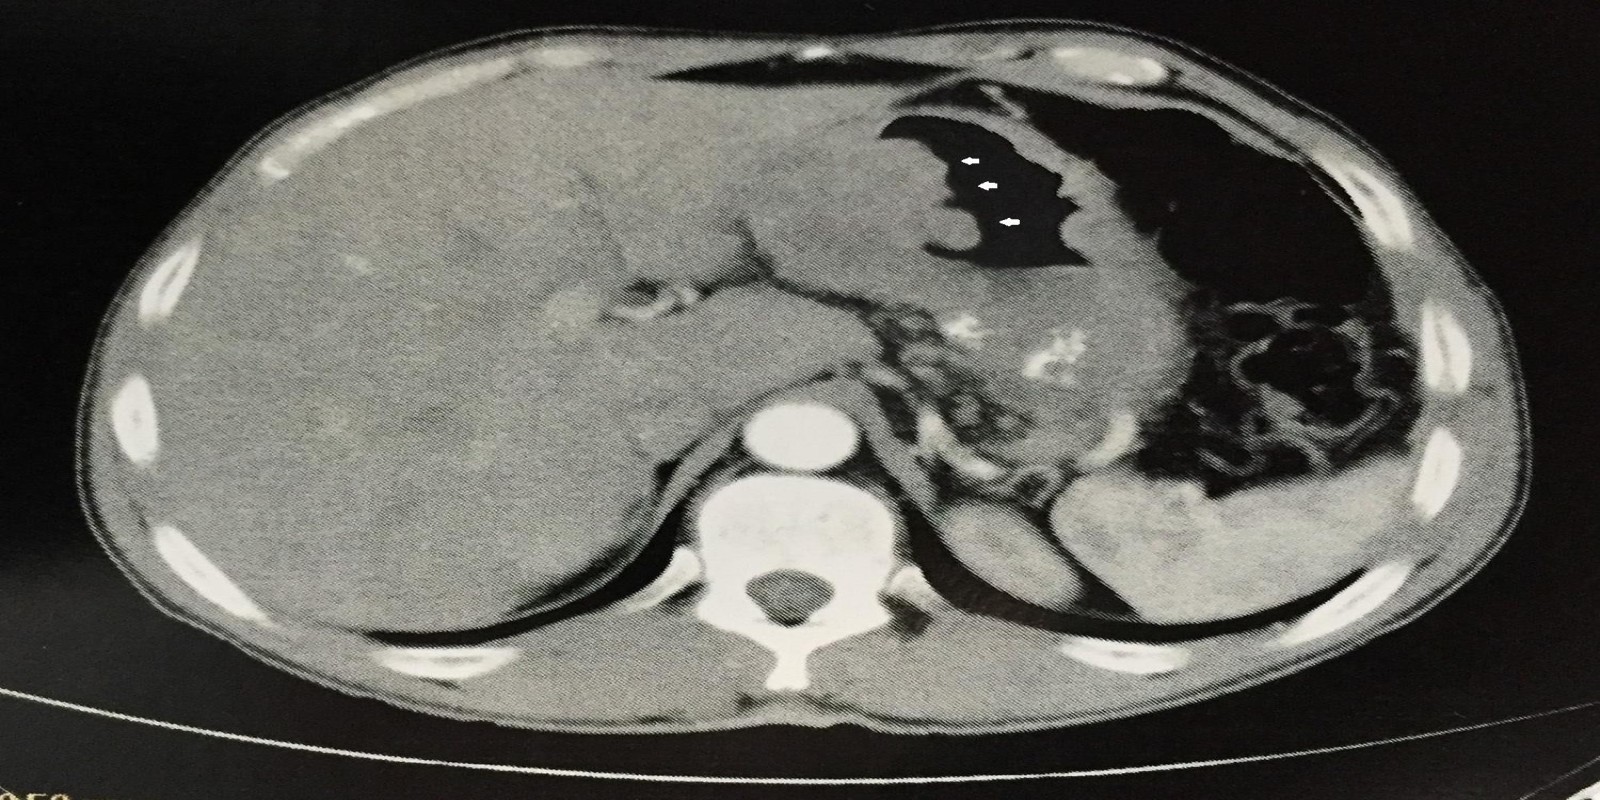

Câncer Gástrico

Gastric cancer